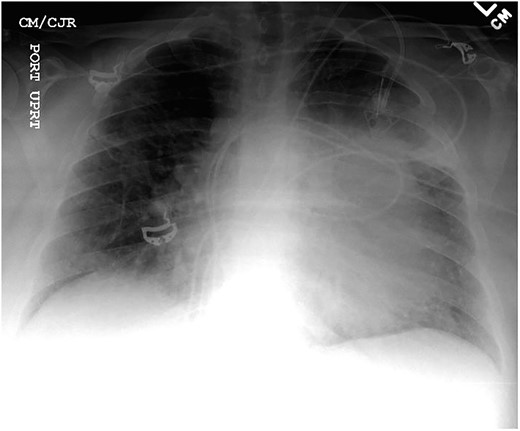

Chest X-ray found an enlarged cardiomediastinal silhouette with mild pulmonary edema (Fig. 1). A computed tomography angiography (CTA) of the chest to rule out pulmonary embolism (PE) was ordered. After the patient returned from imaging, she was found to have a heart rate of 178. Patient was awake, did not appear to be in any more distress and remained hemodynamically stable. Repeated ECG showed monomorphic ventricular tachycardia, with the patient remaining non-distressed. Patient was started on i.v. amiodarone, and urgent cardiology consult was obtained. A transthoracic echocardiogram depicted a large mass measuring 5 cm by 7 cm occupying the basal and mid portion of the anterior and lateral walls of the left ventricles with large pericardial effusion located at the lateral posterior wall of the heart, findings suggestive of impending tamponade (Fig. 2). CTA of the chest reported no acute PE with a large mass (10.5 × 7.5 × 9.5 cm3) occupying the anterior wall of the left ventricle and extending to the pulmonary outflow tract (Fig. 3).

Large ventricular mass measuring 10.5 × 7.5 × 9.5 cm3 invading epicardium and myocardium.